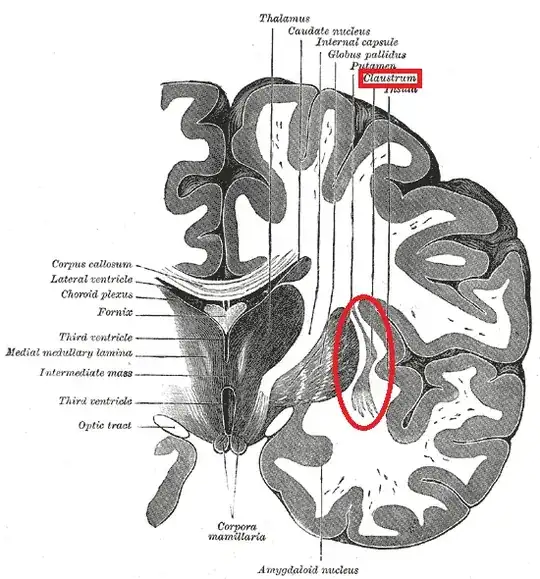

Crick and Koch posited the claustrum (see diagram below) as one of the seats of consciousness in the brain. Koubeissi, Bartolomei, Beltagy and Picard (2014) supported their hypothesis when conducting electrical stimulation mapping on a 54-year-old epilepsy female patient, who became unresponsive under the stimulation in the left claustrum/anterior insula region. However, several limitations in this study need further investigation, such as a high electric current, 14mA and lack of stimulation on right hemisphere.

Now, before you ask how a small strip of gray matter running along between two prominent white matter tracts could essentially "bind" together stimuli from the entire brain consider the following points (drawn mainly from non-human primate and cat data):

The type I cells of the claustrum receive inputs from nearby areas of the cortex, and also have been found to project back

There is significant overlap between the representation of sensory and motor cortices, visual cortices and prefrontal areas, along with motor cortices and prefrontal areas within the claustrum

Interneurons there may possess a more "finely-tuned" timing sensitivity, appropriate for binding together the areas responding to multimodal stimuli

The cat claustrum, in addition to the connections with sensorimotor areas and the visual cortices, also has a prominent section ventral to the visual projections that integrates auditory information

Crick and Koch assert that these points support the idea that the claustrum might be acting as a (orchestral) conductor for multimodal stimuli. Using gap junctions (direct connections between cell membranes, in this case being used as high-speed electrical synapses), interneurons of the claustrum could be employing the type I cells to "grab" and piece together information from disparate portions of the cortex simultaneously.

Of course, once the information is bound together, it would remain to be seen as to which particular structures would interpret this bound data. Crick and Koch don't really comment on this, but since there are strong bidirectional connections with the prefrontal areas, perhaps the "conductor" is also sending back cues upon which the attention of the frontal lobe could be gated, but that is simply an educated guess, and I have no further support for that.

So, as far-fetched as it may seem, a brain structure that is small on volume may have a significant enough representation of cortical information, ability to project back and "conduct" cortical areas, along with an interneuronal backbone capable of precise timing, all of which give it some chance at being an important seat of consciousness in the brain.